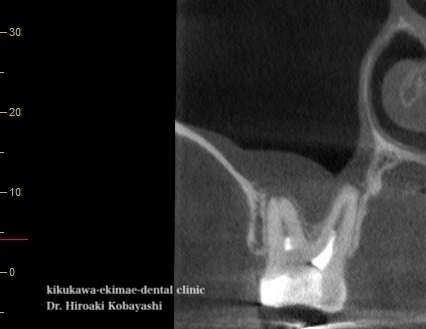

精密根管治療による上顎洞炎の治療

他院にて保険の根の処置を受けていて、中々治らず、上顎洞炎と診断され耳鼻科に受診を勧められ、しまいには抜歯を勧められ、当院にて歯を残すことができないかとご相談を受けました。

2回ほどの根管治療にて、上顎洞炎の病態である粘膜の肥厚も収まり、問題なく治癒しました。